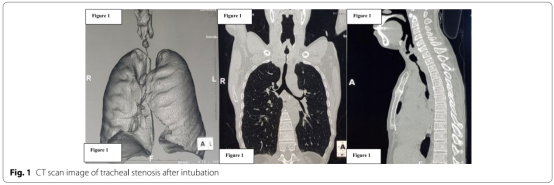

患者评估包括一般病史和体格检查,特别注意气道和肺功能,分析动脉血气。为了在麻醉诱导和维持期间为任何可能的气道紧急情况做好准备,术前必须仔细评估狭窄或肿瘤的准确位置和阻塞程度。计算机断层扫描(CT)提供气管狭窄或肿瘤的最大直径、最小气管直径、病变长度、声带到气管狭窄的距离、从狭窄到隆突的距离(图1).支气管镜检查通过可预测插管和手术容量的直视确定气管狭窄或气管周围肿瘤的特征。